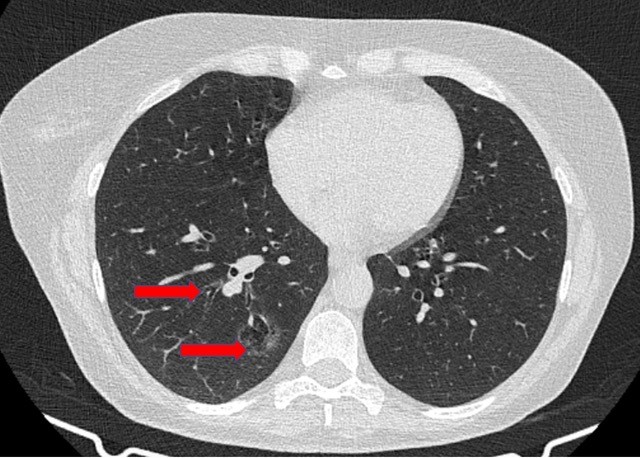

Anatomic sublobar resections have been used primarily for benign pulmonary lesions, lung metastases, and early stage lung cancer. There are many recent studies that support the oncological results of anatomic sublobar resections compared to lobectomy in terms of recurrence and overall survival [1-8]. In addition, the procedure’s performance through minimally invasive procedures is possible by experienced teams [9, 10]. The authors present a sublobar resection performed for a 50-year-old woman who was diagnosed with a 2.5 cm diffuse ground glass opacity adenocarcinoma in the right basal segments (Figure 1) that was identified during chronic asthma follow-up.